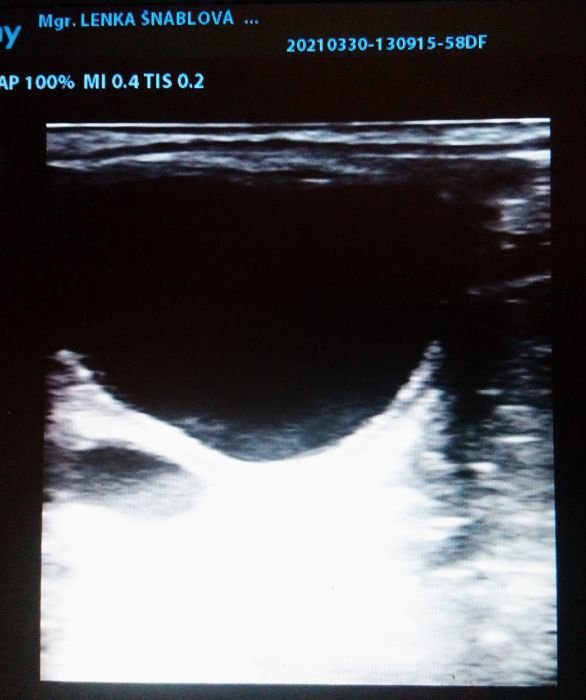

Gravidita klisny 13. den

Gravidita klisny 16. den